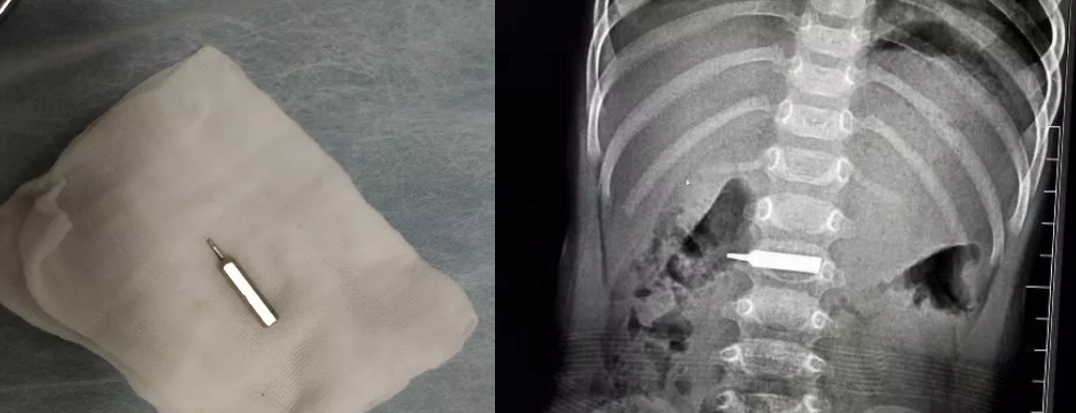

“太惊险了,手术前,这个螺丝刀头一半在胃里,一半已经进入十二指肠,晚一步后果不堪设想。”边鹏介绍,手术还是有很大难度,鹏鹏胃里当时都是食物残渣,手术第一步就是将异物拽回到胃里,这个过程中,异物直接就掉进食物残渣里。”我们先对孩子的胃进行清理,然后才将异物取出。” 边鹏说,手术全程2个小时,很顺利,经过测量,发现异物长约3厘米左右,鹏鹏今天可以喝水了,也可以少量的进食些米汤,明后天就可以办理出院了。